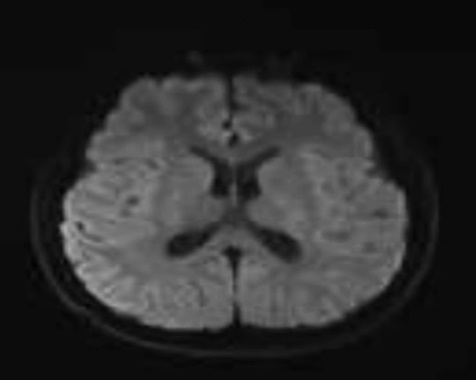

经过入院头颅核磁共振检查提示,小甘胼胝体、两侧内囊后肢、侧脑室体部及后角旁白质异常信号,经神经内科医生会诊后转至神经内科住院。

治疗前